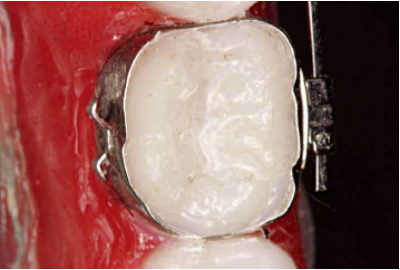

1、上颌带环需要带有口外弓管,下颌带环舌侧选择带蝴蝶翼的。这样方便在后期必要的时候进行磨牙交互牵引(图5,图6)。

2、试带环的时候,不要选择过紧的带环,带环太小无法在磨牙牙冠上做调整;带环也不能太大,不要指望用粘结剂充填过大的带环和牙冠空间,过大的带环在矫治过程中很容易脱落。要保证带环的颊管位置应该在磨牙牙冠的临床冠中心,带环颊管的近中边缘应与磨牙的近中颊尖中央脊对齐,颊管与磨牙近远中颊尖连线平行(图7)。